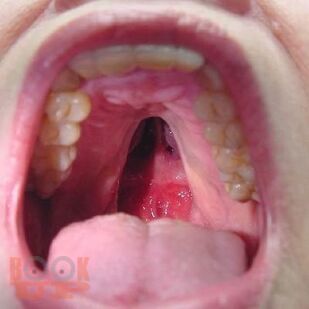

Данное пособие содержит материал, отражающий современные данные о лечебно-диагностических концепциях основных врождённых и приобретённых хирургических заболеваниях детского возраста. В пособии раскрыты ключевые позиции, этиологии, патогенеза, классификации, клинических проявлений, диагностики, консервативного и хирургического лечения, возможных осложнений и исходов хирургических заболеваний у детей. Сделан акцент на эмбриопатогенез и пренатальную диагностику врождённых аномалий развития у детей. Пособие содержит перечень вопросов для самоконтроля, тестовые задания и ситуационные задачи.

Изображения 175